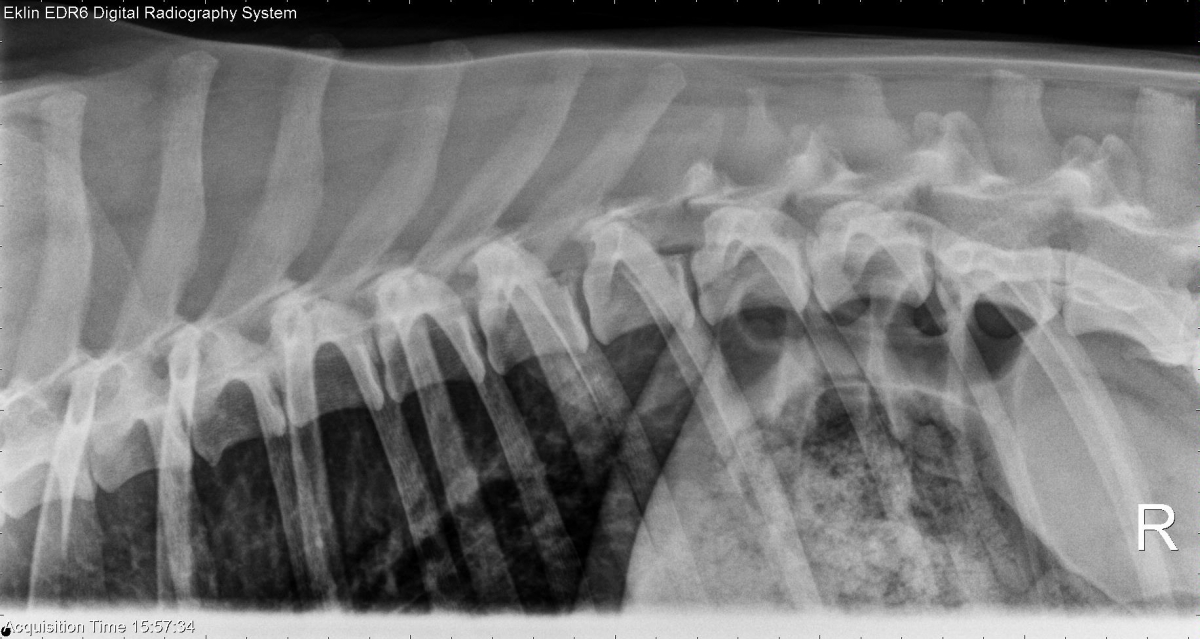

This week’s case is an 8-year-old female neutered Labrador Retriever with a mass on the caudal mandible. Can you see all the lesions?

R LAT Thorax

The cardiovascular structures are normal in size and shape. There are two large soft-tissue nodules in the lungs and multiple smaller nodules. One of the larger nodules is located in the left caudal lung lobe, and the second is superimposed over the trachea on both projections. There is a broad-based soft-tissue opacity in the dorsal thorax, ventral to T10-11. On the ventrodorsal projection, the proximal portion of the 10th left rib is lytic, and a partial curved soft-tissue opacity is visible. Collimated views confirm the extrapleural sign and lysis of the 10th rib.

Pulmonary and musculoskeletal metastatic disease from the oral tumor

Histopathology was inconclusive (melanoma, squamous cell carcinoma, osteosarcoma).